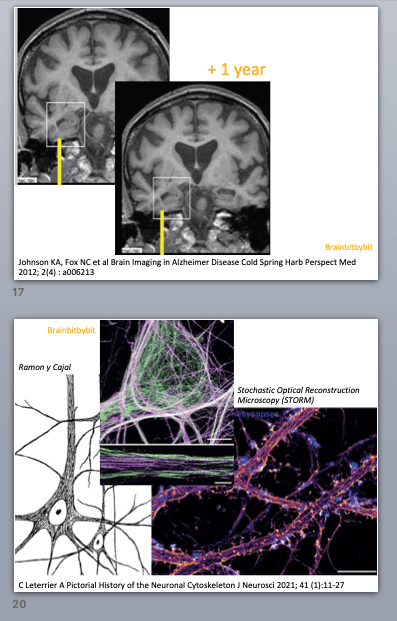

In the nineteen-sixties American neuroscientist Paul MacLean came up with an oversimplified and therefore practical and popular model of the brain. MacLean discerned 3 parts: the brainstem and basal ganglia, the limbic system and the neocortex.

1. The brainstem and basal ganglia were called the “reptilian brain”, involved in instinctual responses.

3. The neocortex or “human brain” houses all the higher brain functions such as language, mathematics, abstractian and thoughts. This makes up (only) half of the human brain volume.

2. The limbic system consists of the parts at the border of the brain stem and neocortex in the cerebral hemispheres. The limbic system is involved in emotion and memory and was called the “mammal brain” in the triune brain model.